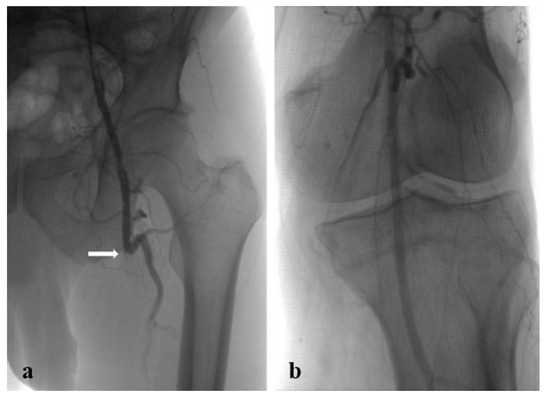

It was decided to proceed with a US-guided approach via the right common femoral artery with 6 Fr introducer sheath after local anaesthesia (Lidocaine Hydrochloride 2%) and systemic heparinization (5000 UI). A preliminary angiogram through the introducer sheath confirmed CT findings and highlighted the widespread atheroma of the common iliac-femoral axis and medium-grade stenosis in the external iliac artery. The right-left crossover was performed with a 6 Fr 45 cm introducer sheath conveyed into the left common iliac artery. A left lower extremity arteriogram confirmed the occlusion of the FP bypass with blood supply rehabilitated in the popliteal artery (Figure 3a,b). The peroneal artery was patent and the tibial arteries were not opacified.

Figure 3. Preoperative angiograms: (a) occluded prosthetic FB bypass (white arrow: proximal anastomosis); (b) popliteal artery revascularized by collateral vessels.